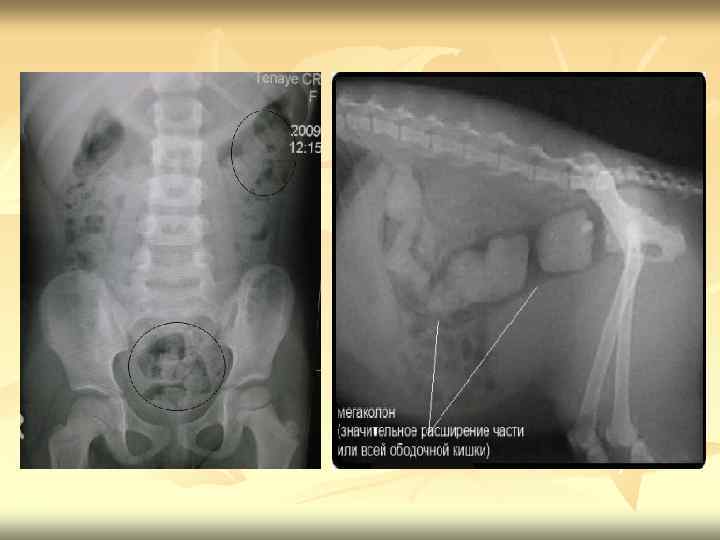

n n n Осложнения запоров Длительно существующий запор может вызывать различные осложнения. Могут возникнуть вторичный колит, проктосигмоидит (воспаление сигмовидной и прямой кишки). При длительном застое содержимого в слепой кишке возможно обратное его забрасывание в тонкую кишку с развитием энтерита (рефлюкс-энтерит). Запоры могут осложняться заболеваниями желчевыводящих путей, гепатитом. Длительные запоры способствуют появлению различных болезней прямой кишки. Чаще всего возникает геморрой. При запорах могут возникнуть также трещина заднего прохода, воспаление околопрямокишечной клетчатки (парапроктит). Длительные запоры иногда становятся причиной расширения и удлинения толстой кишки (приобретённый мегаколон), что делает запоры ещё более упорными. Наиболее грозным осложнением длительных запоров является рак прямой и толстой кишки. Существует мнение, что застой содержимого в кишечнике, вызванный употреблением продуктов, бедных пищевыми волокнами, приводит к большой концентрации образующихся в кишечнике канцерогенных (способствующих развитию рака) веществ и длительному их действию на стенку кишки. Тревожными симптомами, позволяющими заподозрить возможность возникновения опухоли толстой кишки, являются общее плохое самочувствие, похудение, недавнее появление запора у людей старше 50 лет, стул у которых до того был нормальный, кровь в кале.

Диагностический поиск I этап Оценка клинических данных и рентгенологическое исследование кишечника, которое позволит оценить анатомическое состояние прямой кишки: раздражение или нормальное ее строение при функциональных расстройствах, опухоли, аномалии или мегаколон-характерные обструкции, гипоганглиоза, идиопатического расширения. II этап Колоноскопия, гистологическое и гистохимическое исследование биоптатов слизистой оболочки кишки.